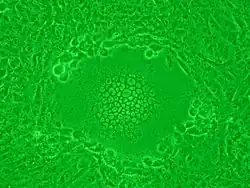

Syncytium caused by HSV-1 infection in Vero cells

Syncytia can also form when cells are infected with certain types of viruses, notably HSV-1, HIV, MeV, SARS-CoV-2, and pneumoviruses, e.g. respiratory syncytial virus (RSV). These syncytial formations create distinctive cytopathic effects when seen in permissive cells. Because many cells fuse together, syncytia are also known as multinucleated cells, giant cells, or polykaryocytes.[13] During infection, viral fusion proteins used by the virus to enter the cell are transported to the cell surface, where they can cause the host cell membrane to fuse with neighboring cells.